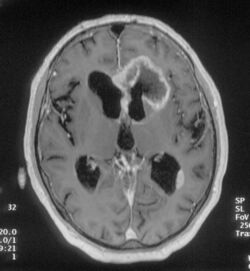

An MRI image of a brain with an invasive, multilocular tumor in the left frontal lobe of the brain.

The origins of frontal lobe seizures can be different deviations.[8] One of the major reasons for FLE is abnormal cognitive development or sometimes congenital abnormal brain development.[8] Other causes are tumors, head trauma, and genetics.[9]